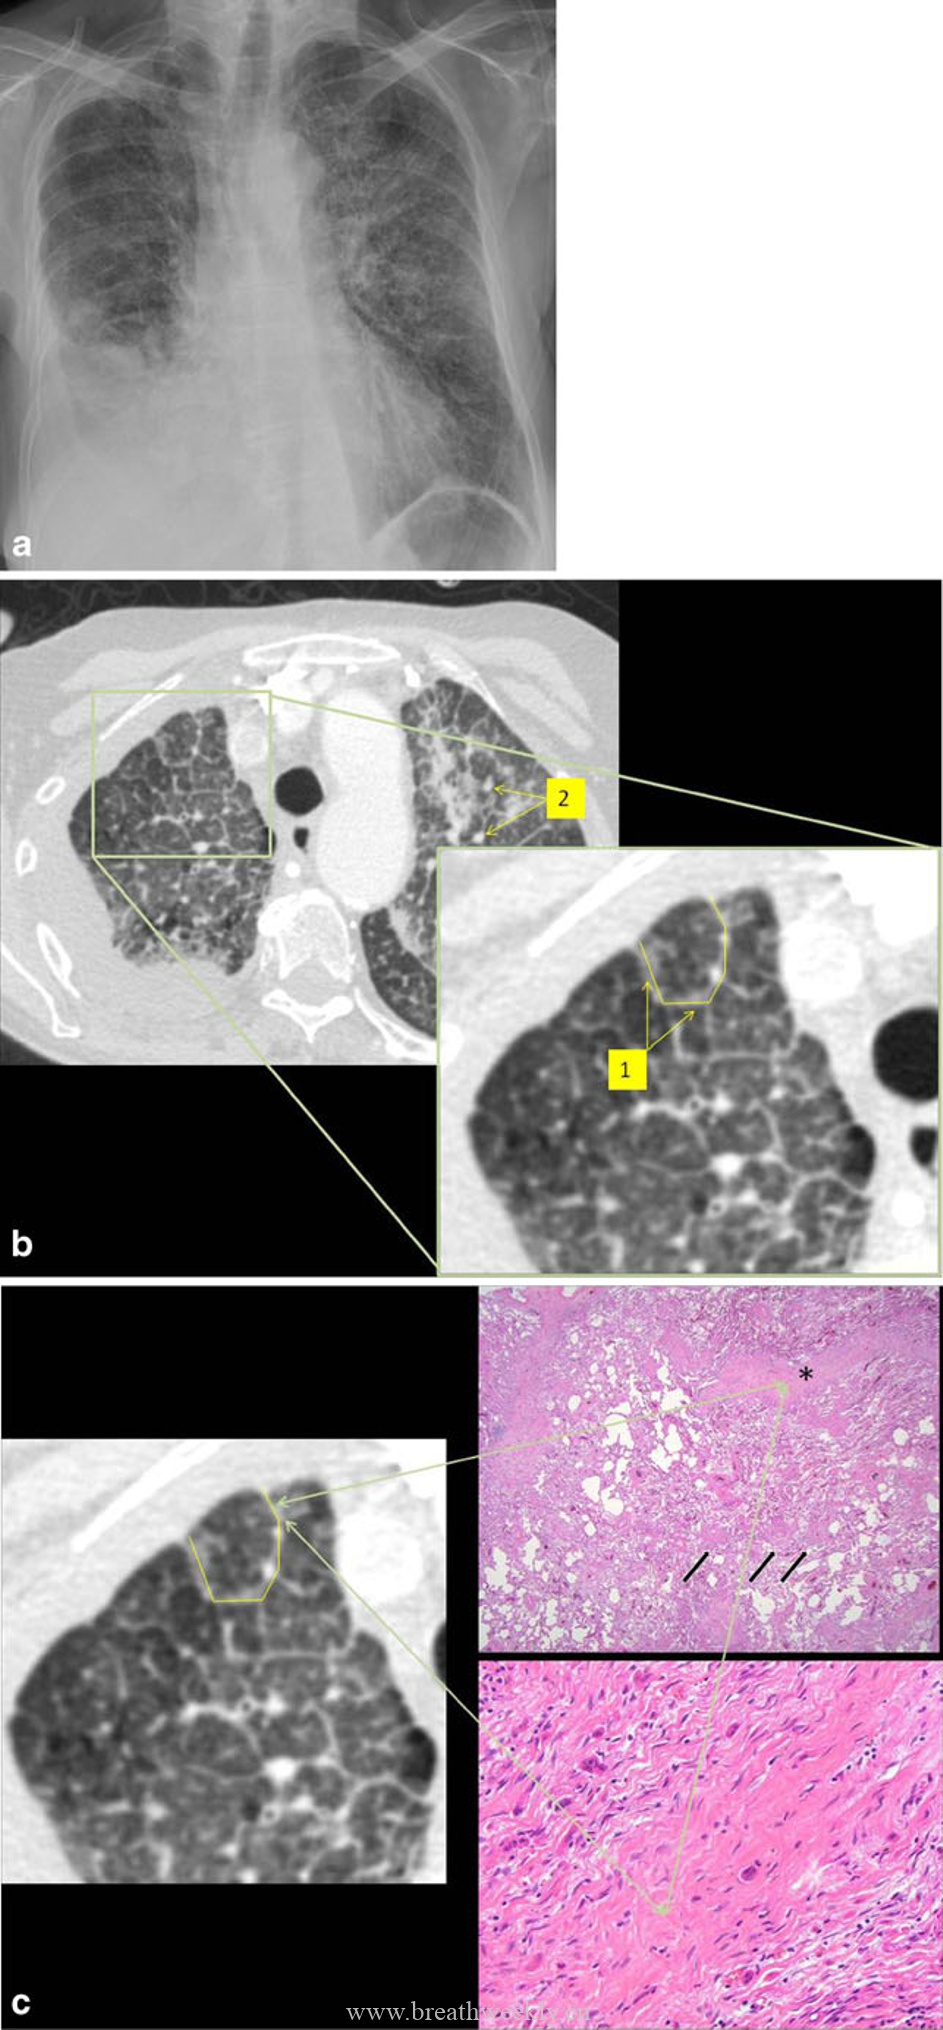

病例3:寻常型间质性肺炎(UIP)

临床资料:80岁男性,快速进展性呼吸困难。

影像表现:CT显示散在分布的铺路石征,伴牵引性支气管扩张。

病理对照:间质增厚,程度不一,部分肺泡隔正常,部分明显增厚,可见蜂窝肺。

UIP的CT特征包括胸膜下网状影和蜂窝肺,从肺尖到肺底逐渐加重。磨玻璃影在UIP中不明显或缺如。组织学标志是时间和空间上不均一的实质纤维化。